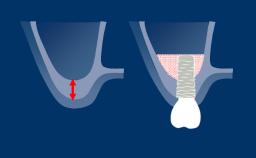

Implants can improve a patient’s quality of life.

There are however various patient dental factors that influence implant therapy and its outcome.

This module describes the relevant dental factors that should be considered when assessing a patient for implant therapy.